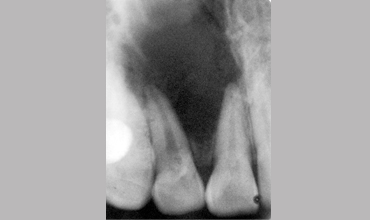

Surgical Management Of Large Periapical Cyst